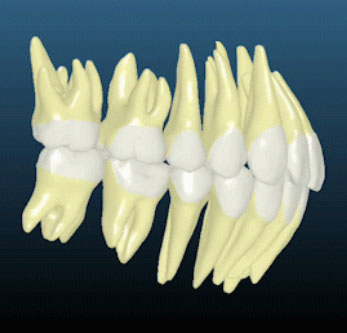

计算机辅助计算结合3D数字化体验,可以精准控制牙齿的移动及咬合调整,完美还原牙齿形态、牙列特点及咬合情况(单颌80-100万数据点);结合CBCT,更可以还原牙根情况,确保安全。

首次突破CBCT真实牙根技术,不仅排齐牙冠更排齐牙根,做到真正的“牙齿”排齐。结合患者骨皮质边界模拟技术,将牙根排列于牙槽骨中心,从而降低正畸复发概率,减小正畸风险。